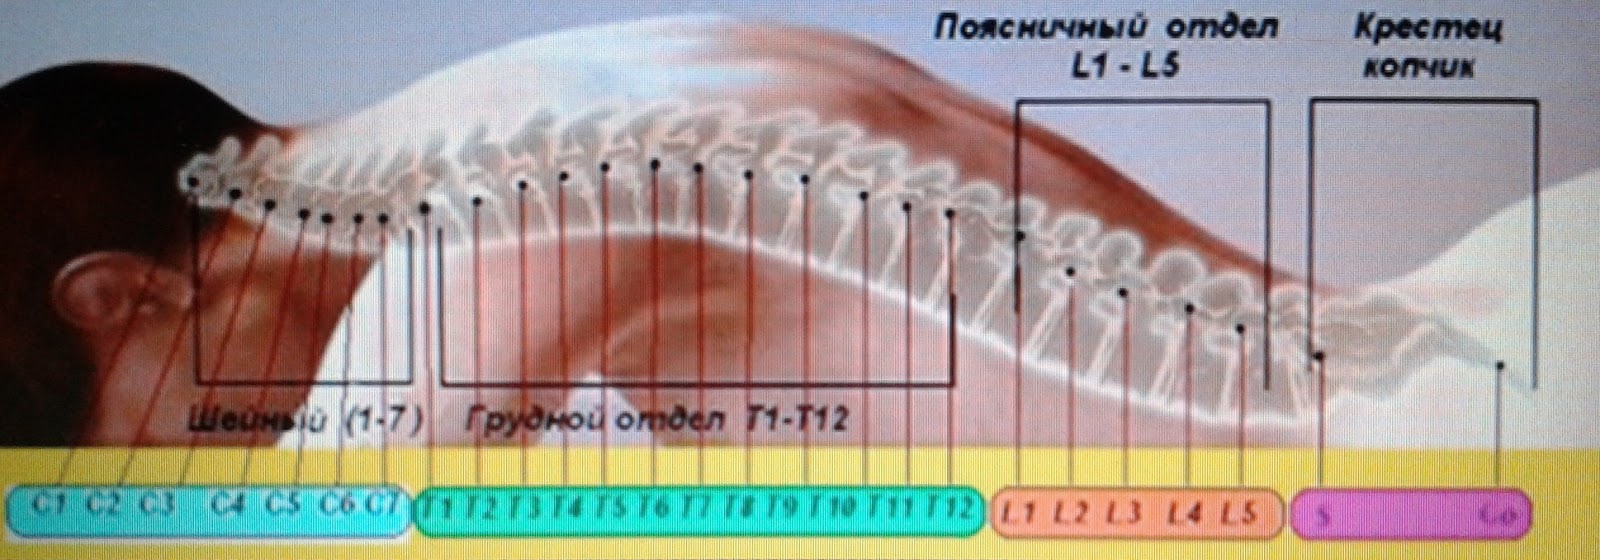

Отделы позвоночника для мрт схема фото и названия